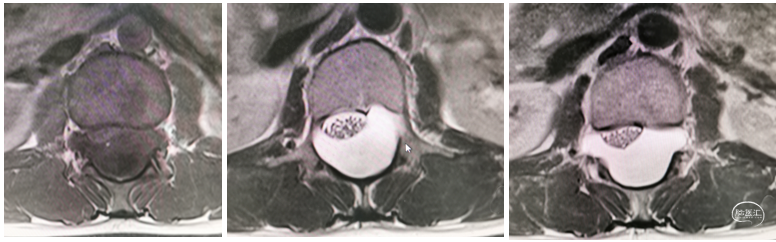

术前胸腰椎CT及MR如下:

图1 胸腰椎CT及MR检查提示:T11-L3椎管内硬膜下异常信号灶,考虑良性,脊髓硬膜内脊膜囊肿?神经鞘瘤?相应脊髓受压等。